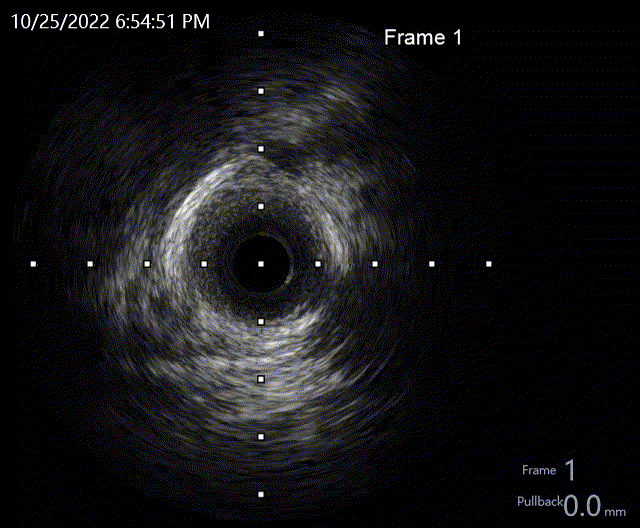

术后LAD IVUS

严重钙化处管腔扩大